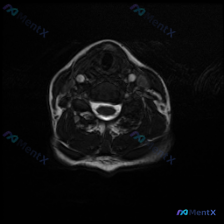

这张图像是颈椎中下段水平的标准T2加权轴位影像,对比度良好无明显运动伪影,影像观察结果如下:

- 椎间盘与骨性结构: 椎间盘后缘与硬膜囊前缘界面清晰,未见明显椎间盘后突;椎体及附件形态对称,无明显骨质破坏或显著增生

- 椎管与脊髓: 中央椎管形态正常,无狭窄;脊髓形态信号均匀,无异常高信号;脊髓周围脑脊液间隙清晰通畅,无受压改变

- 神经根与椎间孔: 双侧侧隐窝及神经根通道空间充足,未见椎间盘突出或骨赘压迫神经根

- 椎旁软组织与其他结构: 椎旁肌肉信号正常,颈动脉椎动脉走行信号无异常,气道居中通畅,未见异常淋巴结或占位

这张影像层面**没有发现支持椎间盘病变(如椎间盘突出、膨出、压迫神经)的客观证据,目前的视觉表现并不提示存在有临床意义的椎间盘病变。